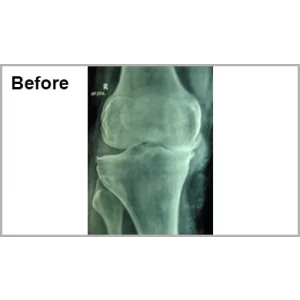

Male aged 60 years had significant difficulty in walking and pain in his right knee. He was operated inform of lumber fusion and right total knee replacement. At present, he absolutely pain free and walking without any support since more than 7 years.